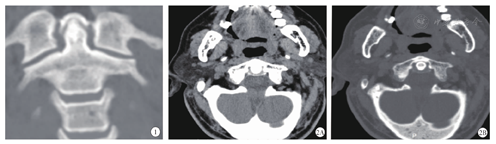

患者男,72岁,以"颈部疼痛活动受限2 d"为主诉入院。查体显示:体温37.6~38.7 ℃,颈椎活动受限,肢体感觉运动无异常,颈痛视觉疼痛模拟评分(VAS)为8分。血液学检查:CRP 12.1 mg/L(0~5 mg/L),余血常规、生化、风湿免疫检查无明显异常。颈椎CT(显示:寰椎横韧带局部钙化(见图1,图2)。依据患者病史、体征及辅助检查,诊断为齿状突加冠综合征(crowned dens syndrome,CDS),给予NSAIDs对症治疗,连续治疗1周后,患者颈部疼痛明显缓解,复查ESR、CRP均恢复正常。随访6个月,患者颈部疼痛无复发。

CDS是焦磷酸钙沉积病(calcium pyrophosphate deposition disease,CPPD)的一种罕见形式[1],由Bouvet等[2]于1985年首次报道。CDS主要是由于齿状突周围韧带组织(尤其是寰枢横韧带)内焦磷酸钙晶体沉积所致,局部释放出基质金属蛋白酶、前列腺素等炎症介质,诱发炎症反应,并出现枕颈部疼痛及活动受限[3]。典型CDS患者在冠状面CT上出现齿状突周围"晕圈样征象(Halo Sign)",因此称为齿状突加冠[3]。

CDS主要表现为急性枕颈部疼痛(100%[8]),可放射至肩部,部分患者表现为头痛,98%患者出现颈部僵硬活动受限(主要是旋转功能),且多伴有发热(80.4%)及炎性指标增高(ESR、CRP)[8]。早期,由于缺乏对CDS的认识,容易误诊为感染性脑膜炎、风湿性多肌痛(CDS患者无骨盆带疼痛、僵硬,有助于二者鉴别[9])、巨细胞动脉炎等[9]。颈椎CT有助于CDS的诊断,横断面可显示横韧带、翼状韧带和黄韧带的钙化情况,而冠状面和矢状面分别能够显示尖韧带和寰椎十字韧带的钙化情况,是CDS诊断的金标准。Takahashi等[5]根据CT横断面上齿状突周围韧带的钙化位置、程度提出了"半定量标准",用于评估寰枢横韧带的钙化情况。除了枕颈区局部症状外,少数患者可能出现寰枢关节不稳、脊髓受压、四肢瘫痪等,MRI检查有助于评估脊髓压迫情况。2001年,Doita等[10]和Assaker等[11]分别报道了齿状突背侧焦磷酸钙沉积导致椎管狭窄,脊髓受压的病例。此外,Malca等[12]提出了无症状的单纯影像学表现为齿状突周围韧带钙化的齿状突加冠。之后,Viana等[13]也有类似报道,多是在体检中发现。Anno等[7]回顾性分析了1 136名无症状的健康人群,40名(3.5%)患者存在寰枢横韧带钙化,认为退变和炎症是主要的机制。

CDS的诊断主要基于临床症状、生物/影像学表现及治疗反应,三者缺一不可[14,15]。CDS因颈部僵硬疑似脑膜炎,行腰椎穿刺者报道较多[14]。临床中,CDS并不罕见,而国内报道甚少,我们认为增加对CDS的认知是早期诊断的关键环节,同时可能避免不必要的有创性操作检查。对于伴有发热的急性颈部疼痛病例,尤其是老年患者,颈椎CT检查(包含寰枢关节二维重建),有助于CDS的诊断,同时能够排除齿状突骨折(齿状突骨折是高龄人群颈椎骨折最常见的部位[16],CDS合并齿状突骨折的病例亦有报道[17]),CDS诊断明确者可给予NSAID抗炎对症治疗。